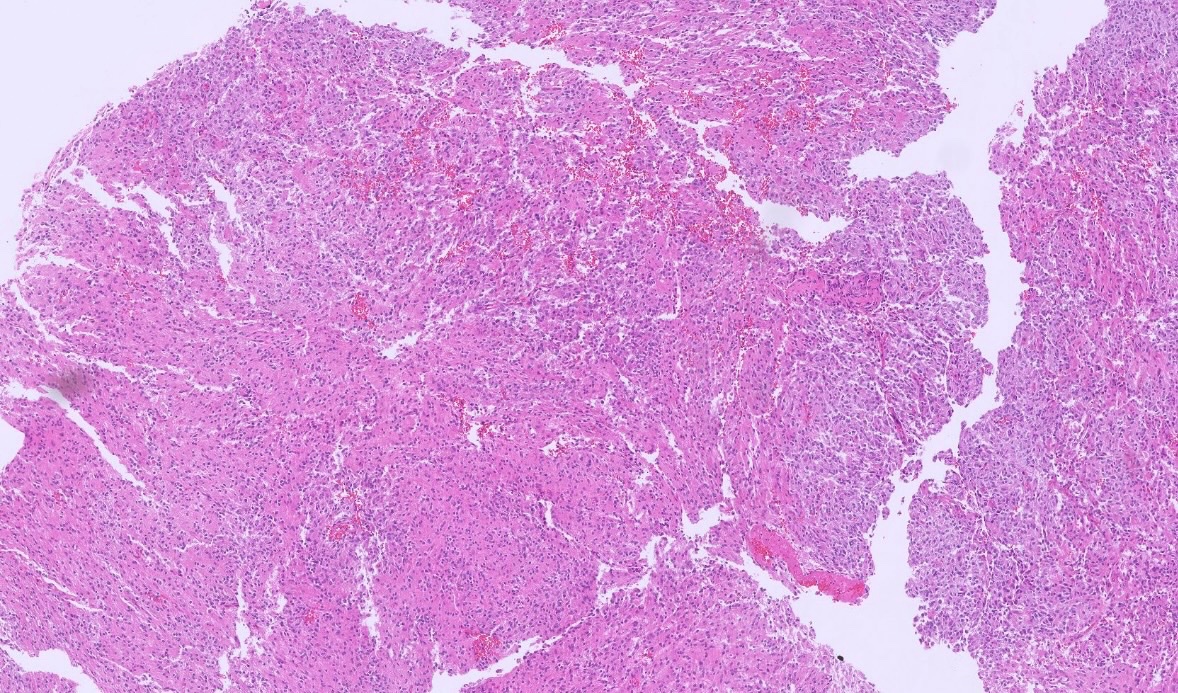

The @neuropathology poster walk at #USCAP2026 was a great success! It was wonderful to see all of the #neuropath representation and connect with colleagues.

The official X account of the American Association of Neuropathologists (AANP)